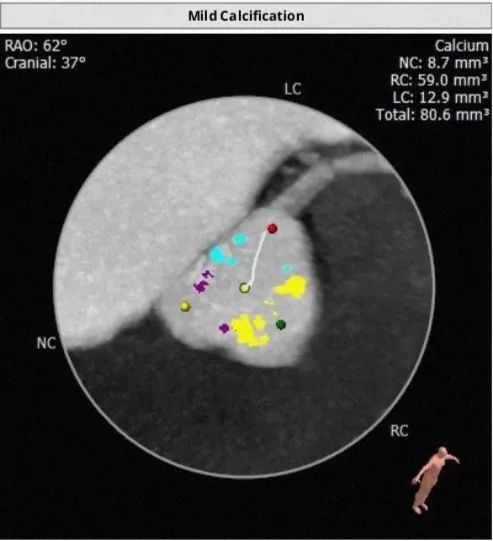

FEops评估冠脉风险

根据FEops报告上的左右冠脉CT截面得知RCA Height:16.0mm、LCA Height:16.0mm,冠脉阻塞风险比较低,通过植入前后的3D模型对比瓣叶形态可以进一步验证。

钙化积分及分布